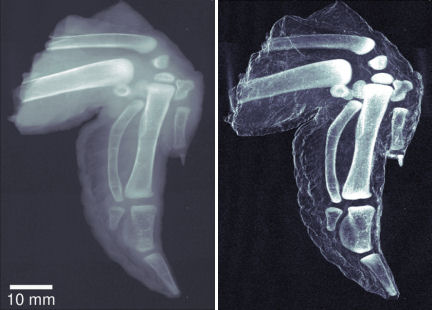

While cheese is smooth, plastic explosive has a microscopic granular structure that increases the scattering of X rays, so its image appeared brighter in tests. The researchers also imaged chicken wings, with the bones revealed in greater contrast than with conventional X-ray imaging thanks to their porous structure. With improvements, the technique might detect tumors, which tend to scatter X rays more than healthy tissue does, Pfeiffer says.